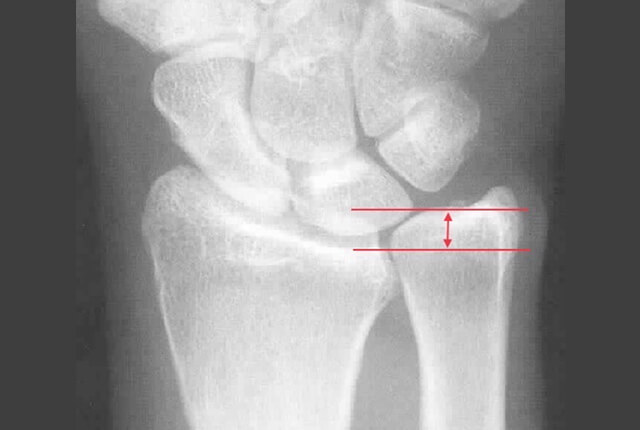

尺骨が相対的に橈骨よりも長い(plus variance)状態である尺骨突き上げ、症候群に合併することもあります。

• 単純X線でplus variance

尺骨短縮術

plus varianceでDRUJ不安定性がない症例に行います。